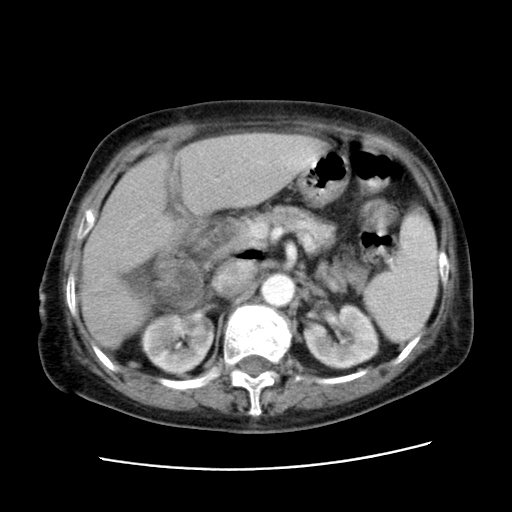

考虑胆管癌

本人考虑胆管细胞癌

肝右叶肝内胆管结石并肝内胆管扩张。胆总管下段梗阻,考虑壶腹部占位。

右侧肝内胆管局限性扩张,其内密度不均匀,扩张的胆管壁增厚,考虑肝内胆管炎合并结石可能性大